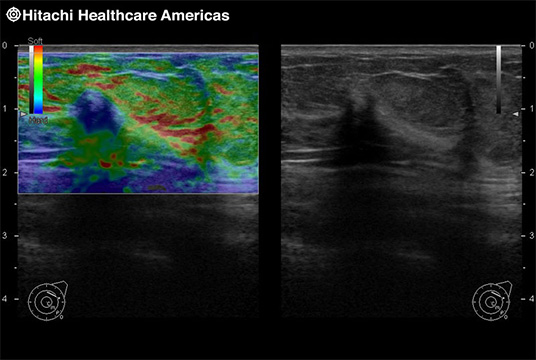

Fujifilm Healthcare's dedication to Surgeons provides outstanding ultrasound technology, professional support and the specialized tools necessary to best perform comprehensive real-time ultrasound imaging in Breast Surgery, General Surgery, Laparoscopic Surgery, Neurosurgery, Robotic Surgery and Surgical Oncology.

Recognized for our outstanding image quality, outstanding system reliability and intuitive use of cutting edge technology, Fujifilm Healthcare remains the standard in the field of Surgery.

Recognized for our outstanding image quality, outstanding system reliability and intuitive use of cutting edge technology, Fujifilm Healthcare remains the standard in the field of Surgery.